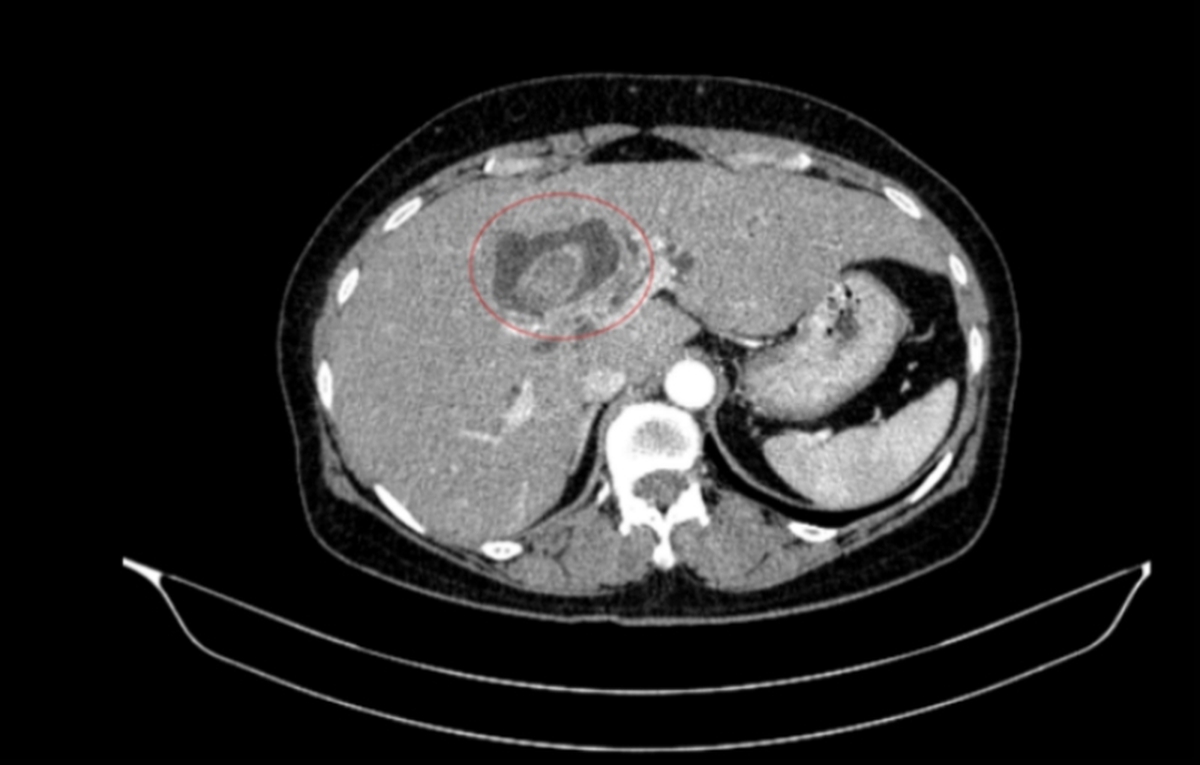

Bệnh nhân được chẩn đoán mắc hai bệnh ung thư khác nhau sau khi thăm khám vì vàng da Tiền Phong+1. Thông tin chi tiết về loại ung thư và giai đoạn bệnh chưa được công bố.

Vàng da là triệu chứng ban đầu, dễ nhận thấy nhất, khi da và lòng trắng mắt chuyển sang màu vàng Tiền Phong+1. Nguyên nhân gây vàng da có thể do nhiều bệnh lý khác nhau, bao gồm các bệnh về gan, mật và ung thư.